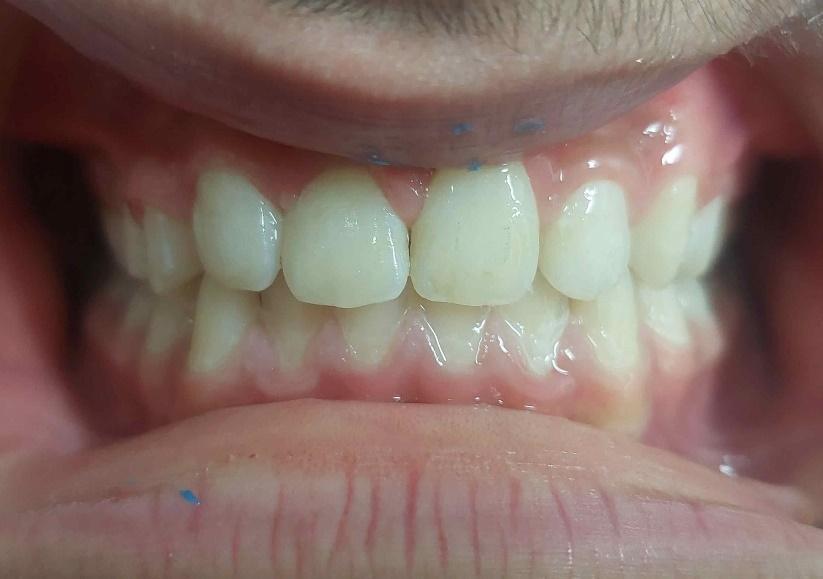

Μετά το πέρας της ορθοδοντικής θεραπείας, (2η φωτογραφία), τα κενά που δημιουργήθηκαν

από την έλλειψη των μονίμων δοντιών μετά την φυσιολογική απόπτωση των νεογιλών δοντιών, έκλεισαν με ορθοδοντική παρέμβαση